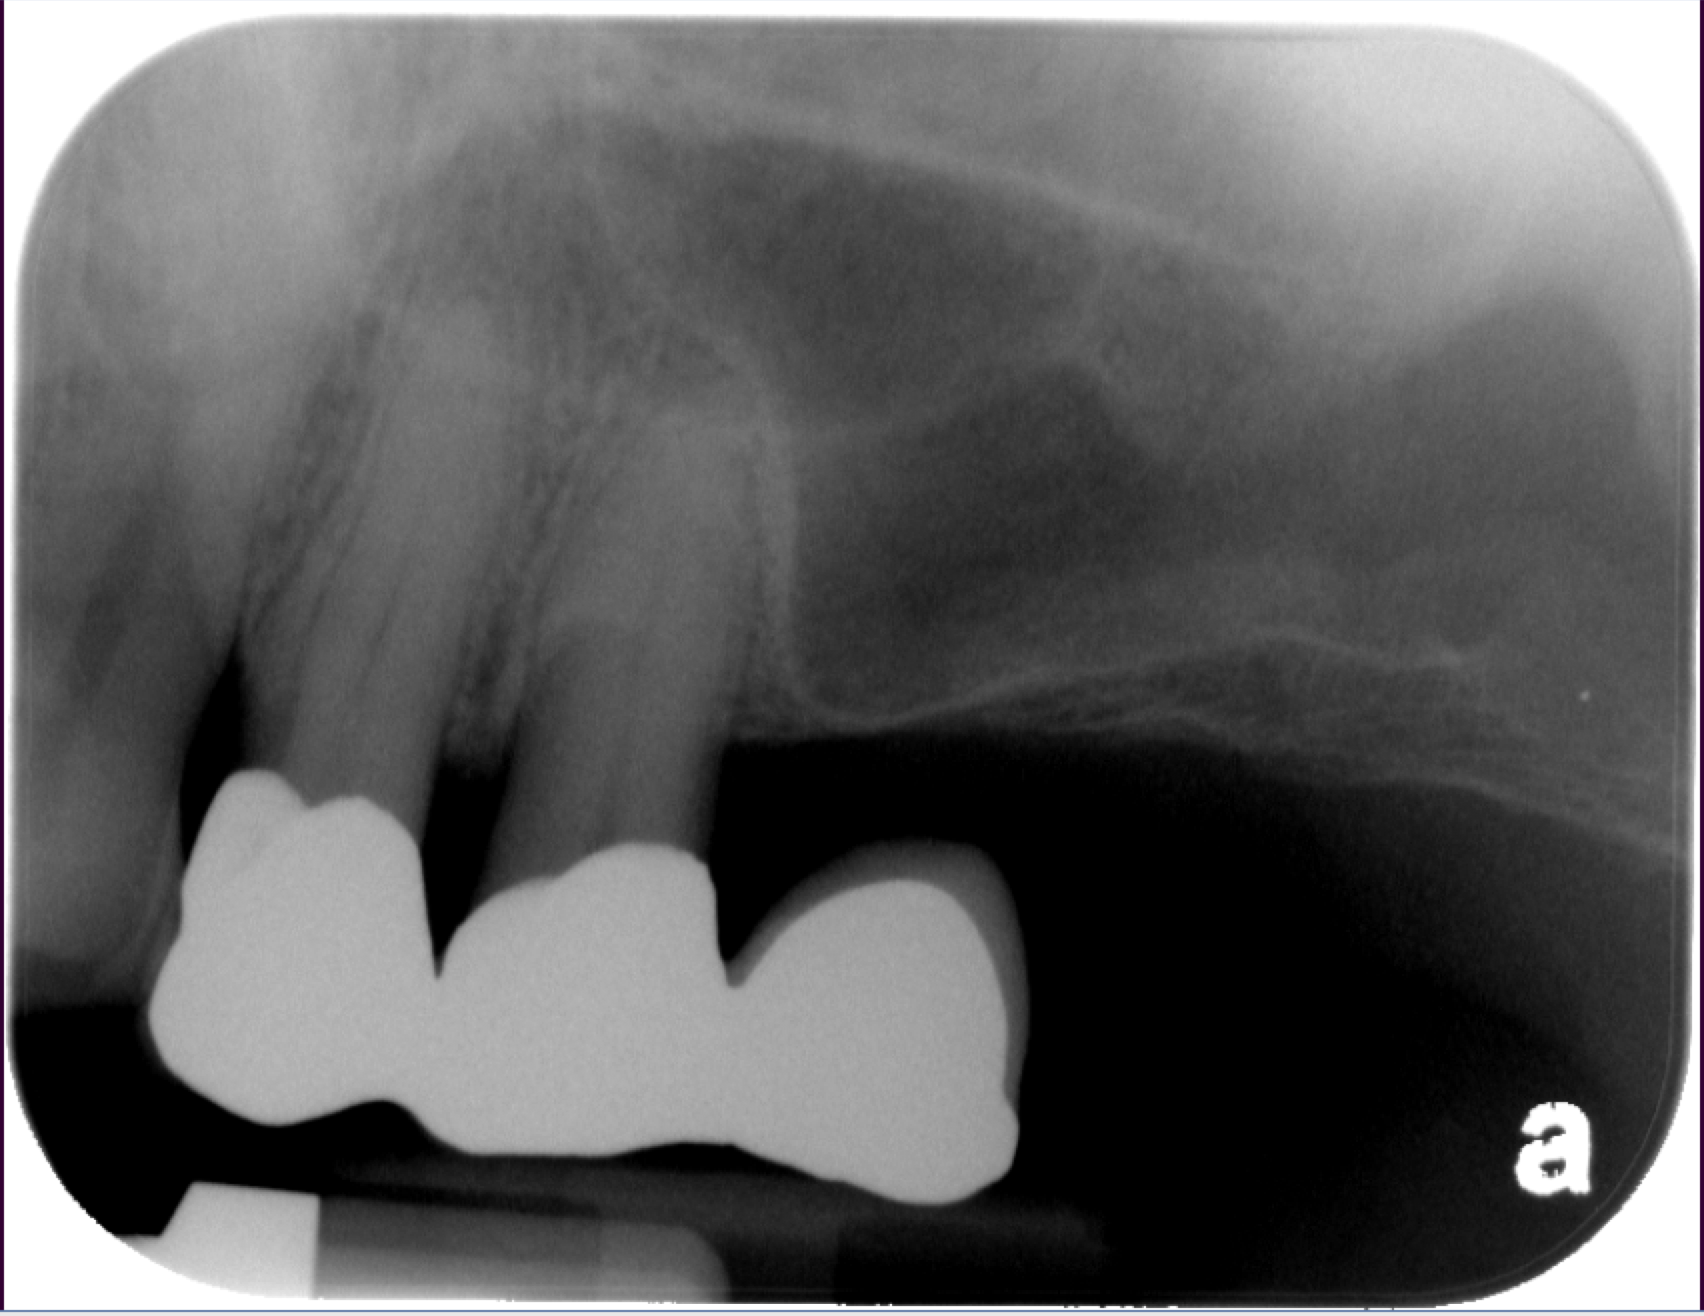

The sinus graft makes it possible for many patients to have dental implants in the upper back teeth area when years ago there was no other option besides wearing loose dentures. The maxillary sinuses are behind your cheeks and on top of the upper teeth. These sinuses are empty, air-filled spaces. Some of the roots of the natural upper teeth extend up into the maxillary sinuses. When these upper teeth are removed, there is often just a thin wall of bone separating the maxillary sinus and the mouth. Dental implants need bone to hold them in place. When the sinus wall is very thin, it is impossible to place dental implants in this bone.

The key to a successful and long-lasting dental implant is the quality and quantity of jaw bone to which the implant will be attached. If bone loss has occurred due to injury or periodontal disease, a sinus augmentation can raise the sinus floor and allow for new bone formation.

The bone used in a sinus lift may come from your own body (autogenous bone), from a cadaver (allogeneic bone) or from cow bone (xenograft). You will need X-rays taken before your sinus lift so the dentist can study the anatomy of your jaw and sinus. You also may need a special type of computed tomography (CBCT) scan. This scan will allow the dentist to accurately measure the height and width of your existing bone and to evaluate the health of your sinus.